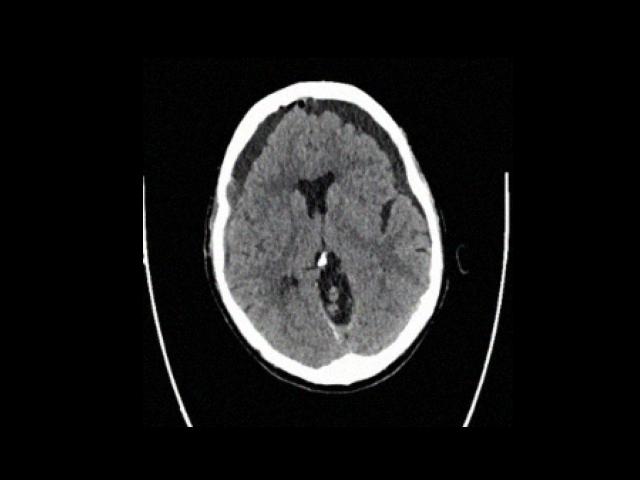

Sample Gallery